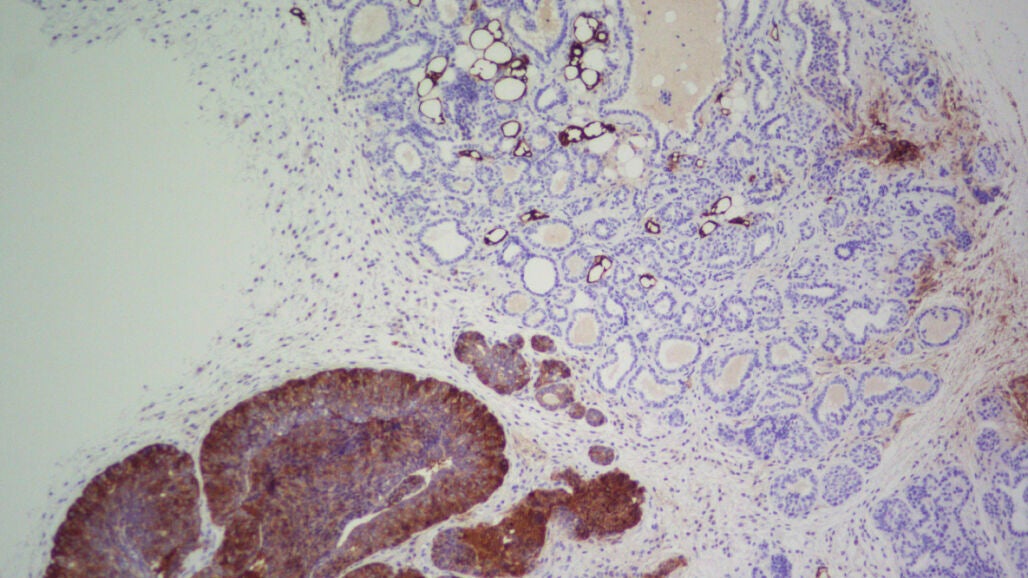

Sin embargo, se sabe que FASN está sobreexpresada en muchos tipos de cáncer, como el de próstata, mama, tiroides, colorrectal, de vejiga, pulmón o páncreas. Por ello, y aunque todavía no se conoce bien su relación con la enfermedad, científicos de todo el mundo lo estudian como potencial diana contra el cáncer.

Ahora, un equipo de investigadores liderados por Miguel Ángel Quintela, jefe de la Unidad de Investigación Clínica de Cáncer de Mama del Centro Nacional de Investigaciones Oncológicas (CNIO), ha descubierto la conexión de FASN con el cáncer y han demostrado que las terapias que la inhiben son altamente eficaces en la fase de formación del cáncer para evitar el desarrollo de los tumores en ratones y en cultivos celulares, y no para tratarlo cuando ya ha aparecido. Los resultados se publican en Nature Communications.

“En nuestro modelo de ratón que desarrolla un cáncer de mama muy penetrante, las zonas en las que hay FASN sí desarrollan cáncer, mientras que en las zonas donde lo bloqueamos no llegaron a generarse tumores y la supervivencia aumentó en un 68 %”, dice Quintela. “Pero cuando tratamos de inhibir FASN con los tumores ya establecidos, hubo un pequeño efecto transitorio que casi no afectó a la progresión”.